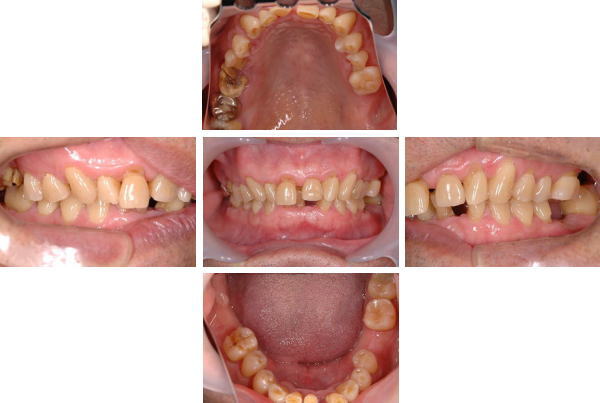

術前の状態

歯周病や歯ぎしり・くいしばりが原因で、歯牙・歯周組織の破壊のみならず顎位のズレまで至ったケ−ス